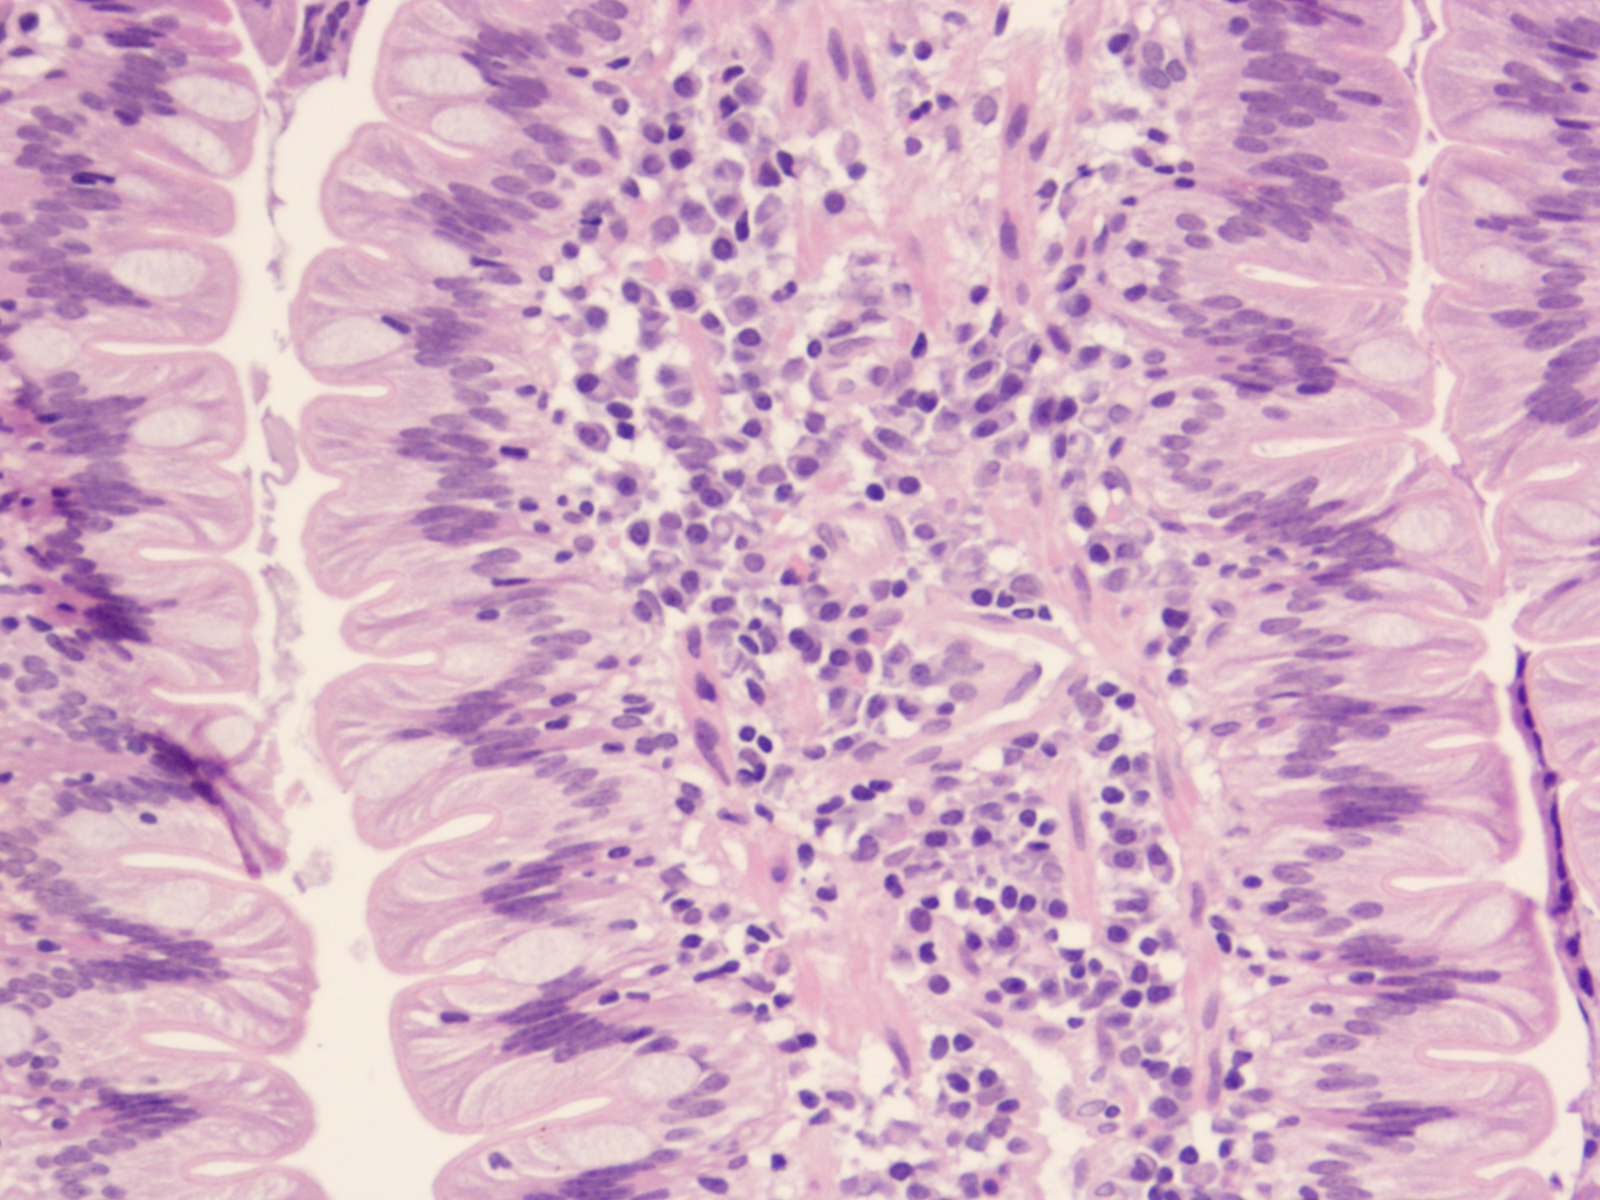

HE-gekleurde coupes van endoscopische duodenum biopten met een lymfo-plasmacellulaire ontsteking (100 x, respectievelijk 200 x). Als gevolg van deze ontsteking zijn zogenaamde cryptabcesjes aanwezig. Dit zijn gedilateerde darmcrypten, die gevuld/overvuld zijn met exsudaat en ontstekingscellen.

HE-gekleurde coupe van een darmvlok in het duodenum. De lamina propria bevat aanzienlijke aantallen gedifferentieerde lymfocyten en vooral plasmacellen, passend bij een lymfo-plasmacellulaire enteritis (200 x).